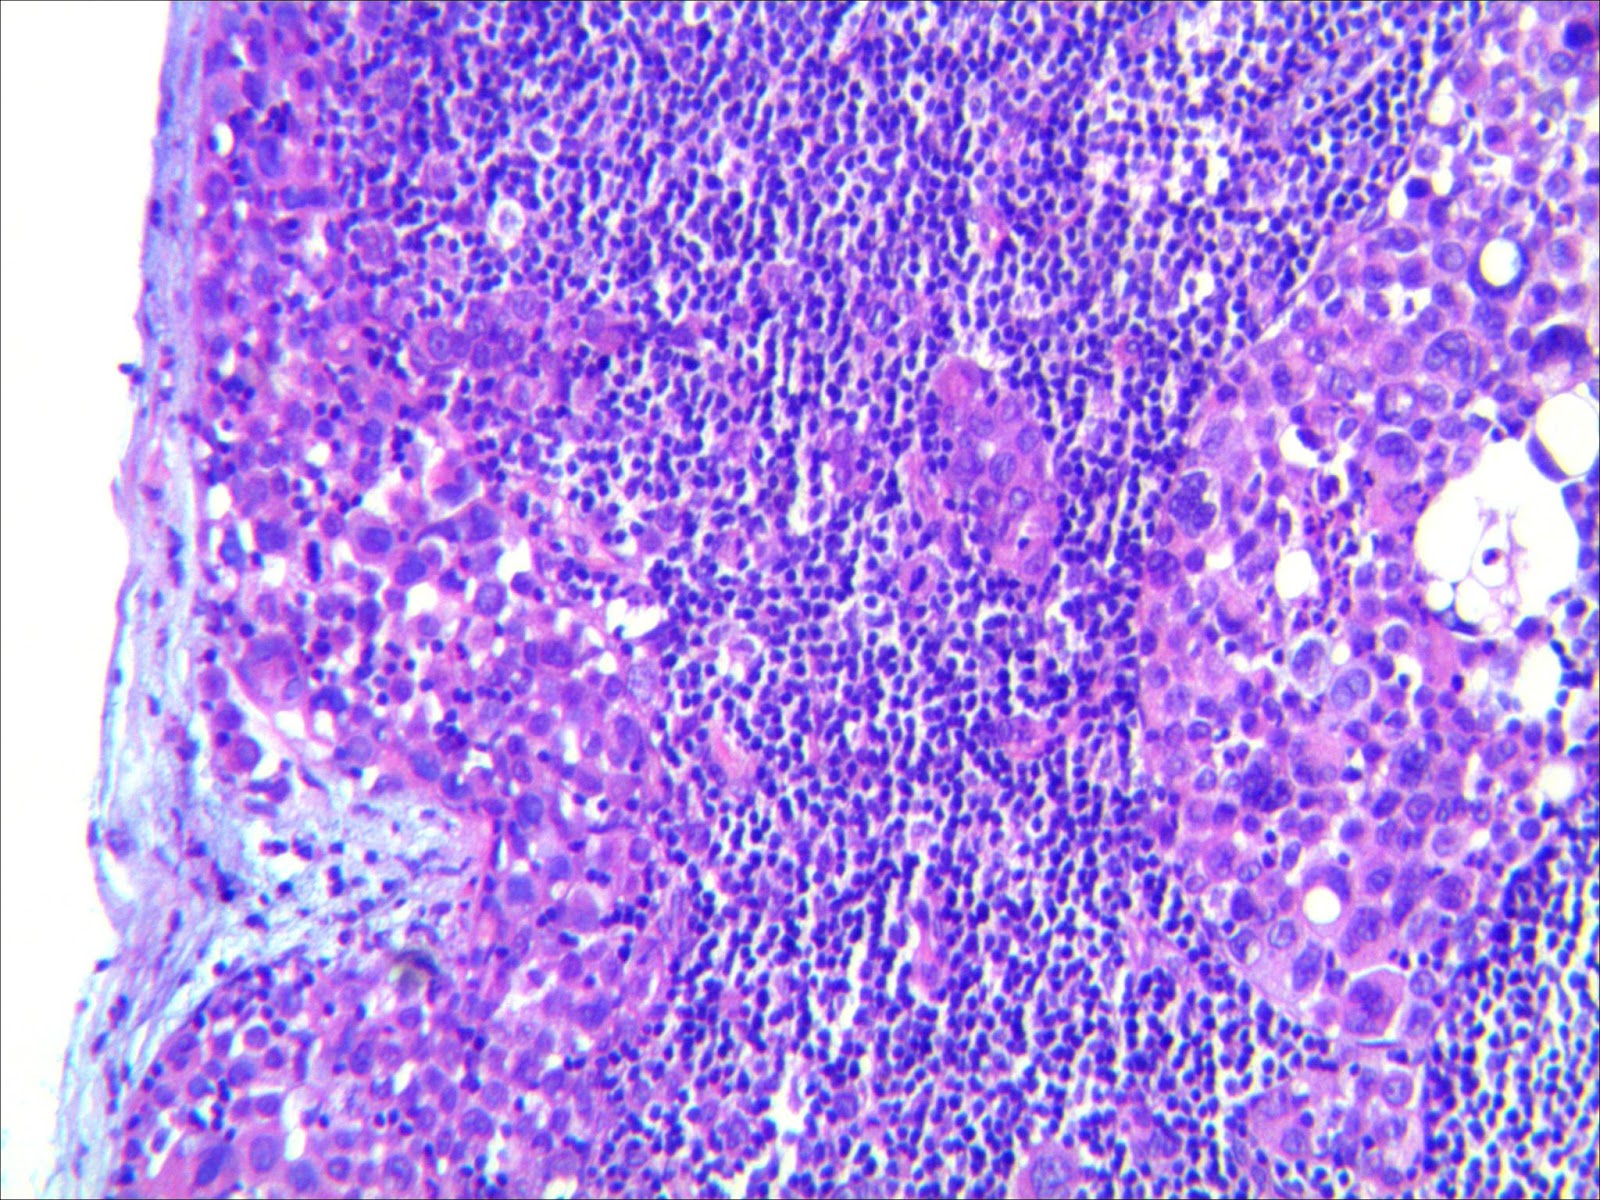

El diagnóstico del ganglio axilar inflamado se realiza mediante la exploración física del área afectada, y a menudo se deben realizar pruebas adicionales para determinar la causa subyacente. Estas pruebas pueden incluir análisis de sangre, biopsias del ganglio linfático y pruebas de imagen, como una ecografía o una tomografía computarizada.